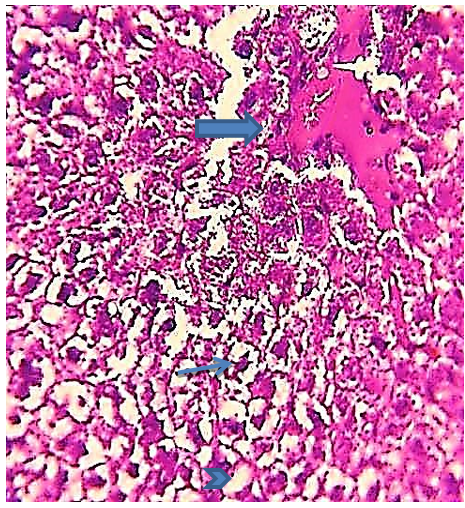

In addition, on day 30, the experiment showed the presence of Kupffer cells, necrotic hepatocytes, hypertrophy of hepatocytes, pyknotic nuclei of hepatocytes, and loss of intercellular demarcation in liver lobules (Figure 5). Also, sinusoidal expansion, acute necrosis, cytoplasm vacillation of the hepatocytes, and nodal inflammatory cell infiltration were observed (Figures 6 and 7).

Figure 6) Liver section of the 2.85 mg CBZ group on day 30 showed sinusoidal expansion (arrow) and clear hepatocytes necrosis (N) (H&E 400X).

Figure 7) Liver section of the 2.85 mg CBZ group on day 30 showed nodal inflammation cell infiltration (circle) (H&E 400X).